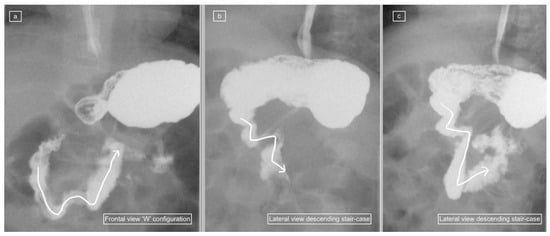

Figure 5.

(a–d): UGIS showing an abnormal duodenum in a 12-day-old boy with non-rotation. (a) Lateral view demonstrates a “slope-like” descent of D2 oriented posteriorly. (b) D3 courses anteriorly from this point. (c,d) represent sequential image captures in the frontal view which show the horizontally oriented D3 with an inferior descent rather than a superior ascent to D4. Most of the small bowel was positioned on the right on follow-up images in keeping with non-rotation rather than malrotation.